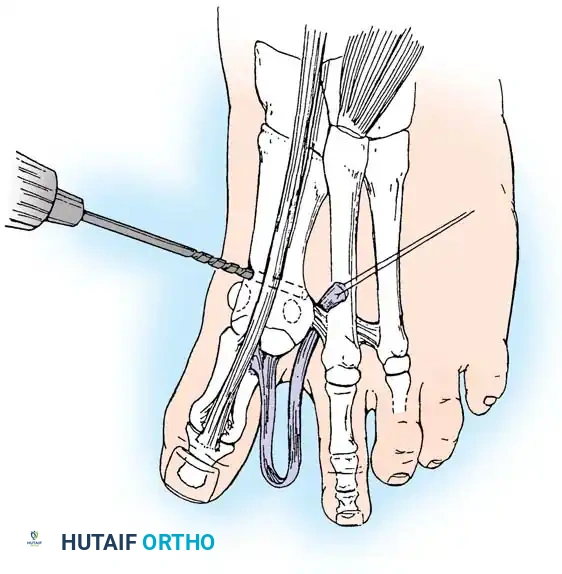

• Grasp the hallux in one hand and displace the proximal remnant medially so that, under direct vision, two longitudinal 0.062-inch Kirschner wires can be inserted.

• Hold the interphalangeal joint straight while drilling the wires from proximal to distal, emerging a few millimeters plantar to the nail plate.

• Return the foot to the corrected position, and drill the wires into the metatarsal head.

• While holding the metatarsal as far laterally as possible, cross the joint, and drive the wires out the plantar cortex just proximal to the head, while holding the hallux in 10 to 15 degrees of extension, neutral abduction, adduction, and rotation, and no translation dorsally or plantarward on the metatarsal head. The wires should penetrate only 2 to 3 mm past the cortex to avoid tenderness over the wires with weight bearing.

• If the Kirschner wires tend to “walk” on the rounded articular surface of the metatarsal head, use a small hemostat snugged up against the wire while it is being drilled to allow accurate placement. Proper placement of the wires and the desired position of the hallux on the metatarsal may require several attempts. The medial aspect of the proximal phalanx should not rest medial to the medial aspect of the metatarsal head.

• Place the hallux in the neutral medial-lateral plane and in 10 degrees of extension.

• Before the second wire is driven into the fi rst metatarsal head, place the hallux in proper rotation, using the plane of the nail as a guide. The initial length of the hallux is maintained by the wires. Later, collapse occurs when the wires are removed, but improved encapsulation of the hemiarthroplasty, by maintaining length for the fi rst few weeks, may help maintain a more desirable position long-term.

• Cut the wires off 2 to 3 mm distal to the skin edge.